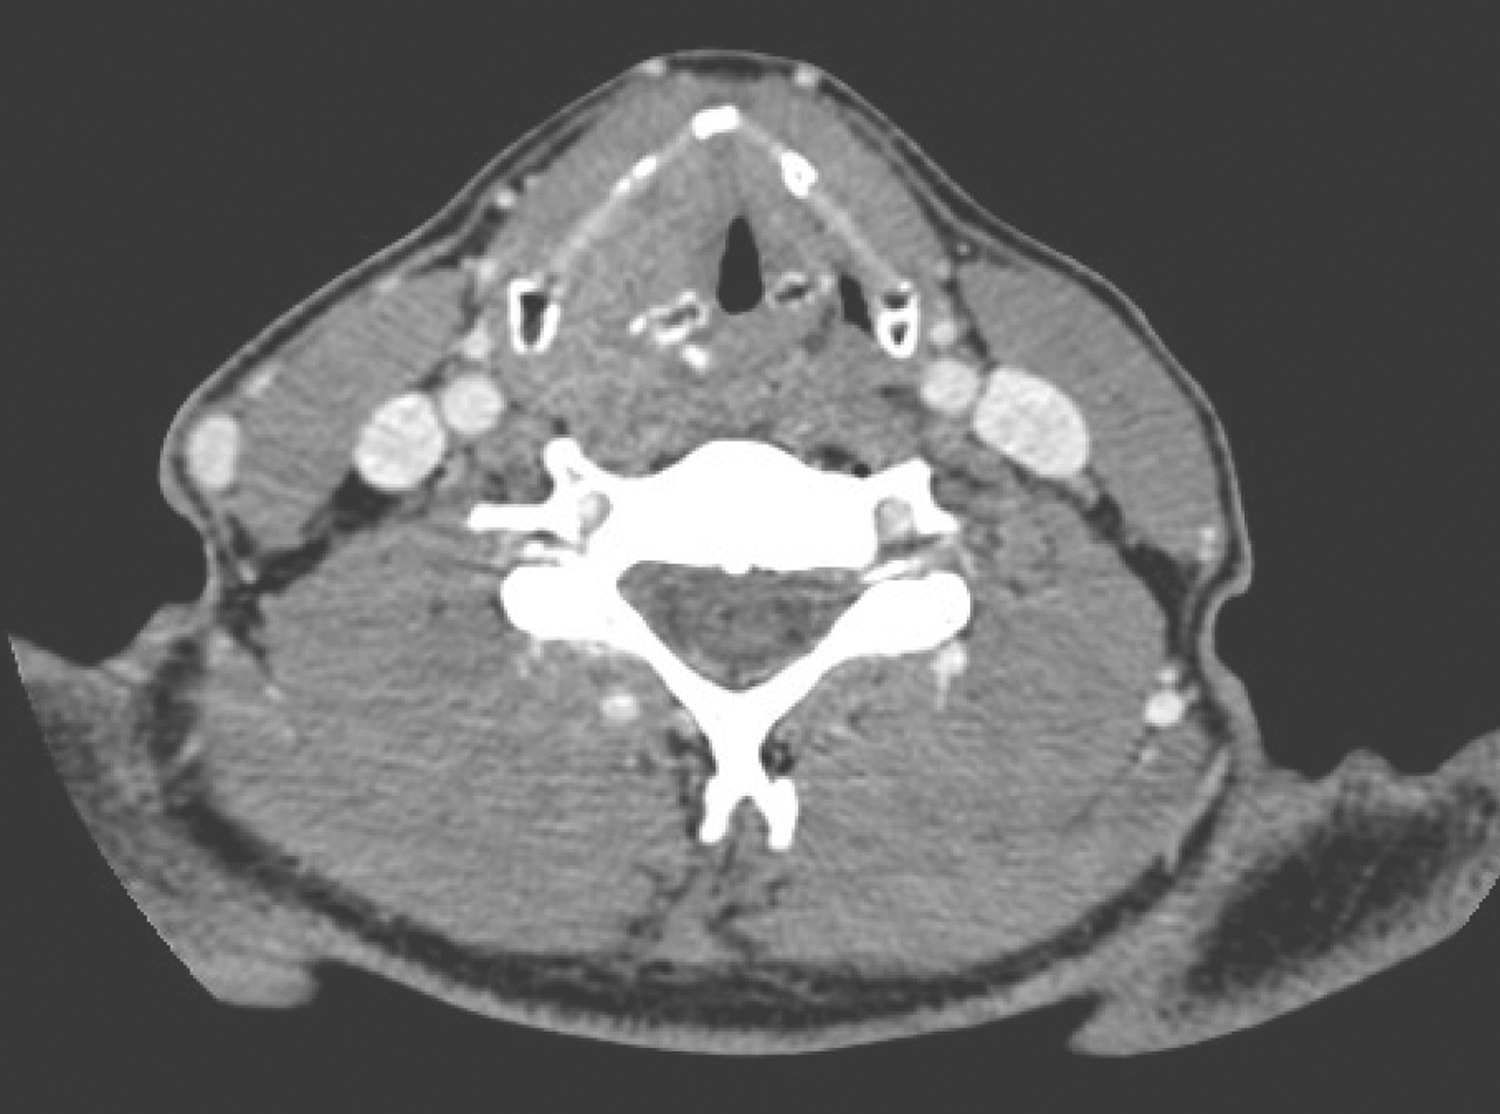

2.2014年1月10日颈胸部强化CT

右侧梨状窝内侧壁、右侧杓会厌皱襞局部软组织增厚,约4cm×3cm,形态不规则,累及右侧声门旁间隙和会厌前间隙,可见强化。右侧Ⅱ区胸锁乳突肌内侧可见数枚肿大淋巴结,约2cm×1.5cm大小,可见环形强化,边界不清(图4~图6),纵隔、双肺门未见肿大淋巴结。CT诊断:下咽恶性肿瘤并颈部淋巴结转移表现。

图4右侧Ⅱ区胸锁乳突肌内侧可见数枚肿大淋巴结

图5右侧梨状窝内侧壁、右侧杓会厌皱襞局部软组织增厚

图6累及右侧声门旁间隙